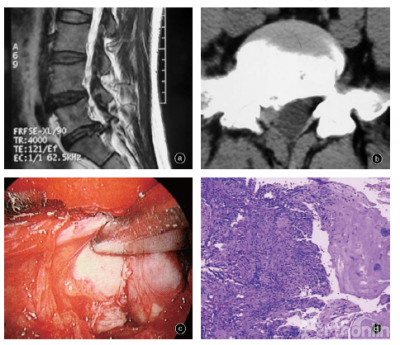

图3 男,42岁,椎体后缘骨软骨病伴椎间盘损伤疝出 a 矢状面MRI T2WI示S1椎体上终板后缘缺损伴L5S1椎间盘疝出 b 横断面CT示椎体后缘骨化物后侧有椎间盘组织疝出 c 后路脊柱内镜术中见突出物质硬(器械所指),髓核自薄弱区疝出并突入椎管 d 疝出的椎间盘组织在光镜下可见纤维软骨基质退变,周围有新生血管及肉芽组织形成 HE染色×200

椎体后缘骨软骨病伴椎间盘突出压迫并向后推移马尾和神经根,渐进性发展,其发病与局部压迫程度、椎管狭窄程度、髓核是否疝出、动态刺激、位置等多种因素有关。青少年退变增生程度轻,有一定的代偿空间;随着年龄增大和退变,后侧黄韧带及关节突关节退变增生加重,与前侧突出物形成相对应挤压产生症状,包括间歇性腰腿痛等,且一旦出现症状往往呈进行性加重。该型可合并椎间盘疝出,髓核自纤维环损伤薄弱区疝出突入椎管,与损伤疝出型致病机制类似:机械压迫、炎性介质和免疫因素导致神经根性疼痛,可看作是损伤疝出型的一种特殊类型(图3)。椎体后缘骨软骨病是较常见的椎体发育异常,常伴有椎间盘突出。因此,对椎间盘突出症患者应注意观察是否合并椎体后缘骨软骨病。

椎体后缘骨软骨病为椎体骺板次发骨化中心发生的骨软骨病,椎体后缘畸形、软骨结节和相邻椎间盘一起突入椎管。曾有人将其称之为椎体后缘离断症、椎体缘骨折、椎体后缘软骨结节、椎间盘骨化等。术中可见椎体后缘与椎间盘一起向后突出,骨软骨性突出为椎间盘突出的一部分,质硬,范围大,为硬性突出,切除困难。突出部分的内压多正常。术中椎间盘造影显示髓核形态可接近正常,侧位片上呈现圆形、椭圆形或马蹄形,比较饱满,但偏向后方,根据椎间盘突出情况也可呈多支分散状或显示纤维环裂隙。

(一)病理学改变

椎体后缘骨软骨病的突出物除椎间盘髓核和纤维环外,还包括软骨终板与骺环形成的成熟板层骨,属硬突出。该病可能与累及腰椎椎体后缘的非典型性Scheuermann病有关。Scheuermann病为椎体环形骨骺的缺血性坏死导致生长障碍和楔形变,有三个或以上相邻椎体前窄后宽楔形变,后凸≥5°,排除外伤史和其他病理改变。有学者将有软骨结节、终板不规则改变及椎体变形,但不满足三个相邻椎体楔形变者称为非典型性Scheuermann病,其基本病变是以Schmorl结节为特征的椎体次发骨骺骨软骨病,在行MR检查的脊柱患者中检出率可高达25.6%。

椎体后缘骨软骨病伴椎间盘突出多发病于骨骺发育成熟前、椎体后缘骺软骨环尚未与椎体骨性愈合的青少年。椎间盘髓核组织在反复创伤或应力作用下突破软骨板的发育缺陷和裂隙,进入椎体与骺环之间并使骺环后移;破裂的软骨板、骺环与椎体后缘分离并逐渐骨化,形成椎体后上缘或后下缘嵴样后突和骨性后壁;相应的椎间盘髓核、软骨板及纤维环后移,形成骨软骨性突出伸入椎管;后移程度较小、骨化程度较高者可与椎体愈合。软骨终板异常使渗透和弥散作用下降,造成椎间盘营养障碍和退变加速、弹性降低而硬度增加,椎体和纤维环异常应力增加,纤维环后外侧形成裂隙,导致椎间盘进一步突出。其病理实质是椎体后缘发育异常部分与椎间盘一起向后突出,与其相对应的椎体后缘骨缺损被椎间盘组织充填。